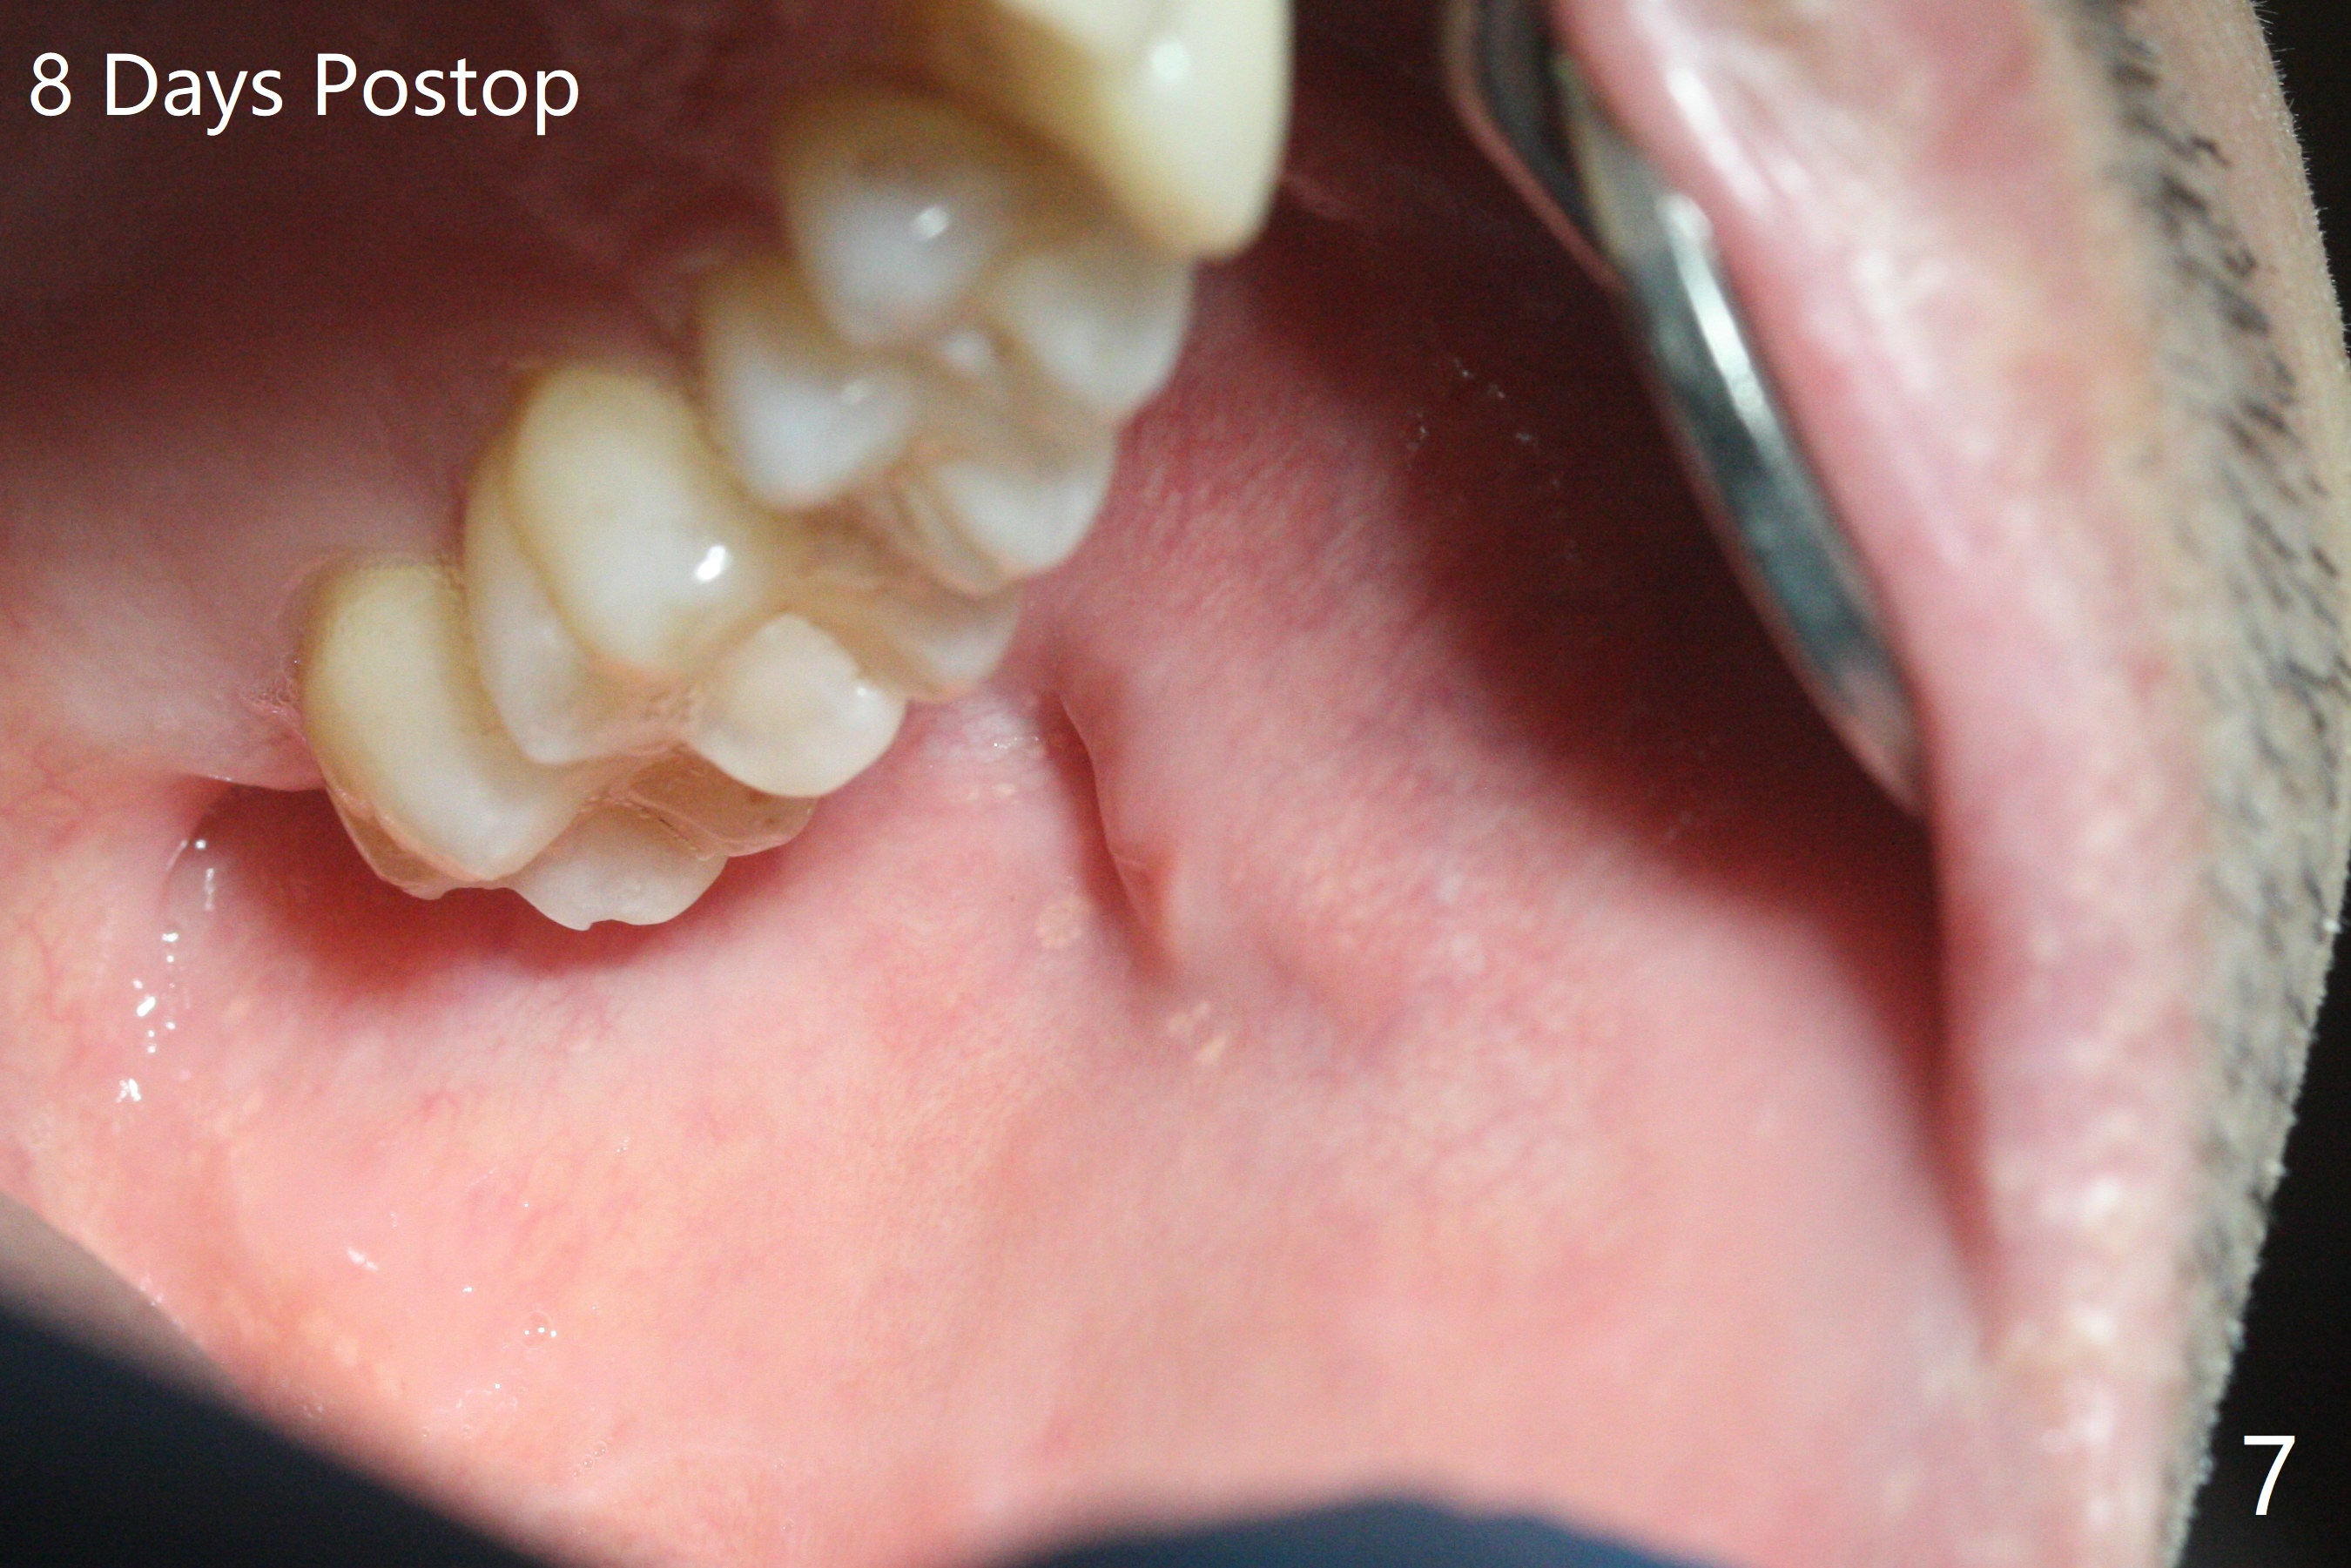

50岁男左侧面部肿痛两个月(图一),服用头孢霉素,最后家庭医生怀疑腮腺炎,需要口外医生诊治,他昨天来我们诊所,口内检查表明左侧腮腺导管口红肿,少量脓液(图二:*),导管口远中粘膜下好像有硬块,便拍摄X光片,显示~4毫米结石(图三),病人积极要求马上治疗,但是当时没空,他只好今天回来。来时说痛极了,口外肿胀中心(图一:箭头)反而硬。口内浸润麻醉后,在导管口远中做一个小切口(图四:黑线),沿着导管方向,锐性钝性分离不久,发现结石,取出(图五)。挤压口外肿胀中心,大量脓液从口内切口流出(图六)。手术当天晚上病人汇报疼痛消失。术后八天在腮腺深部才有压痛,口内导管口周围正常(图七)。Return to Professionals 植牙,导板与正畸 Xin Wei, DDS, PhD, MS 1st edition 12/23/2020, last revision 01/05/2021